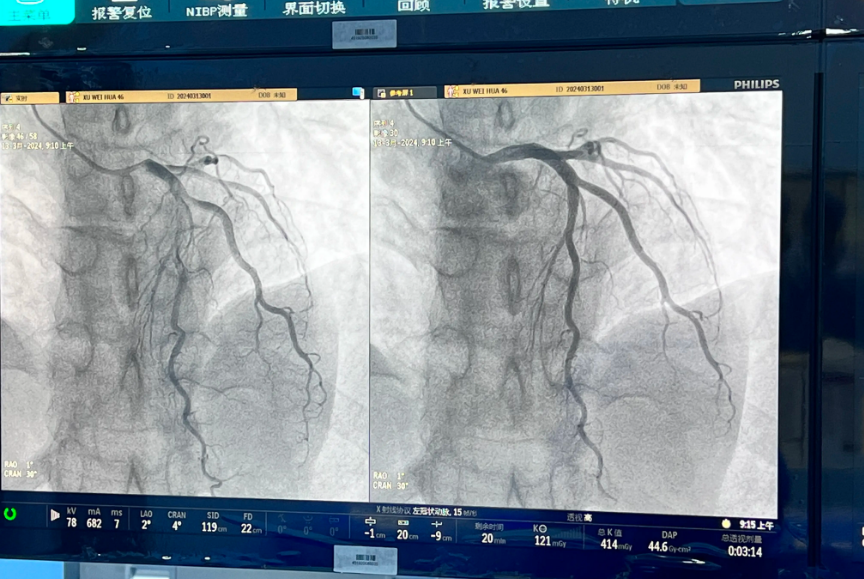

连续用药6个月后,复查冠脉已恢复通畅,不仅免除了搭桥的痛苦,而且身体全面康复,做梦都不敢相信。